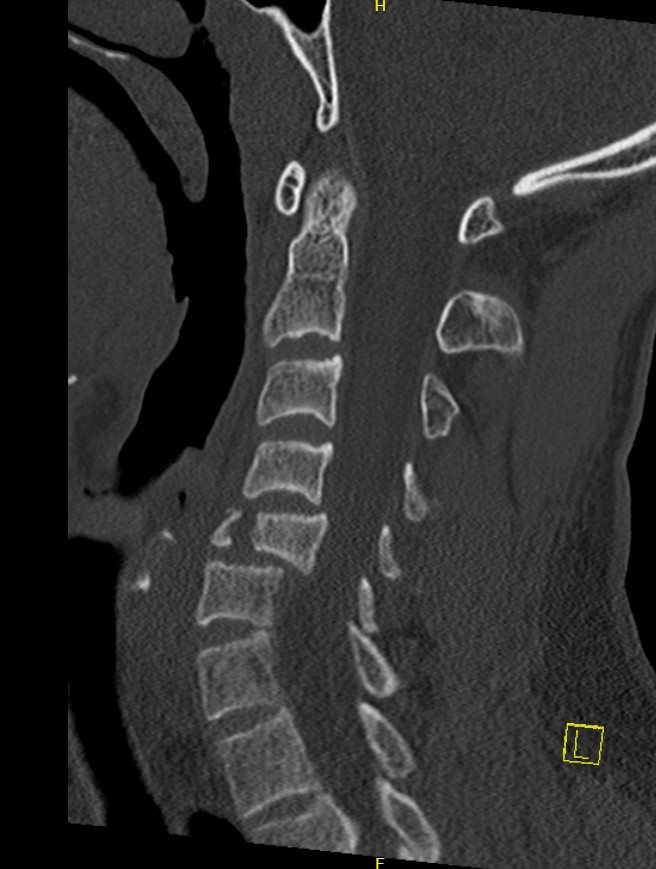

CT

Injury to anterior and middle columns, with retropulsion +/- posterior column

Pathology

Anterior & middle columns fail

- if severe, posterior ligament complex fails

Canal compromise / neurological injury

- retropulsed fragments

- typically one or two main retropulsed fragments